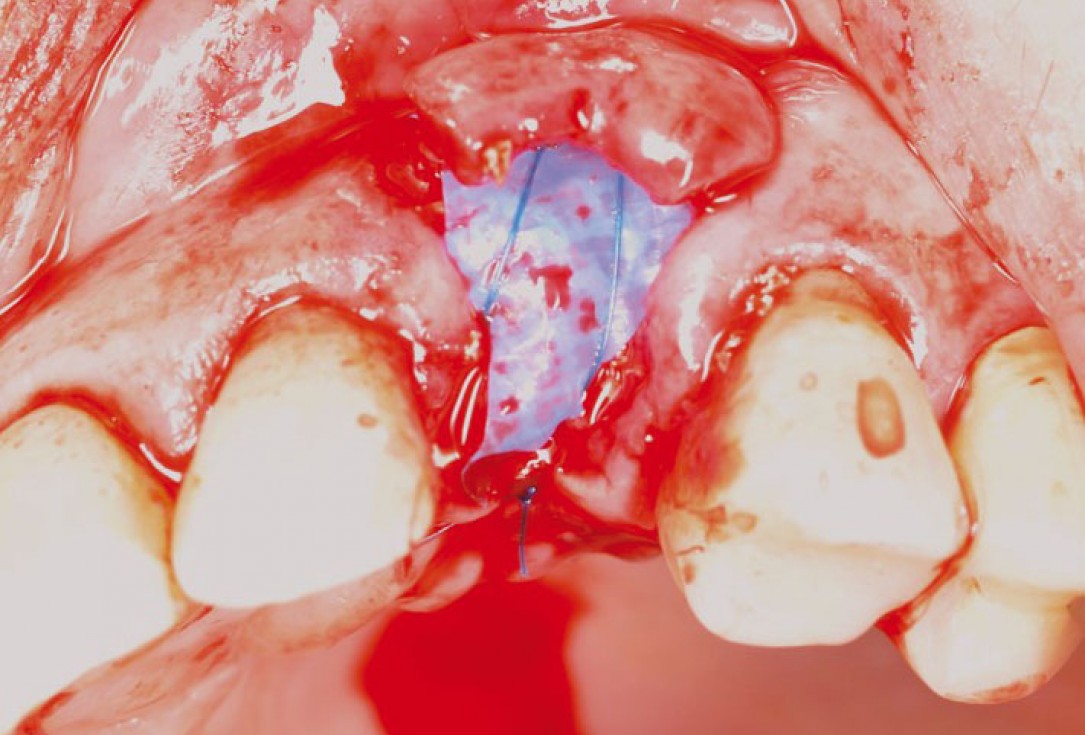

GBR with cerabone® and Jason® membrane in the front tooth region - Dr. H. Maghaireh

Initial clinical situation with gum recession and labial bone loss eight weeks following tooth extraction